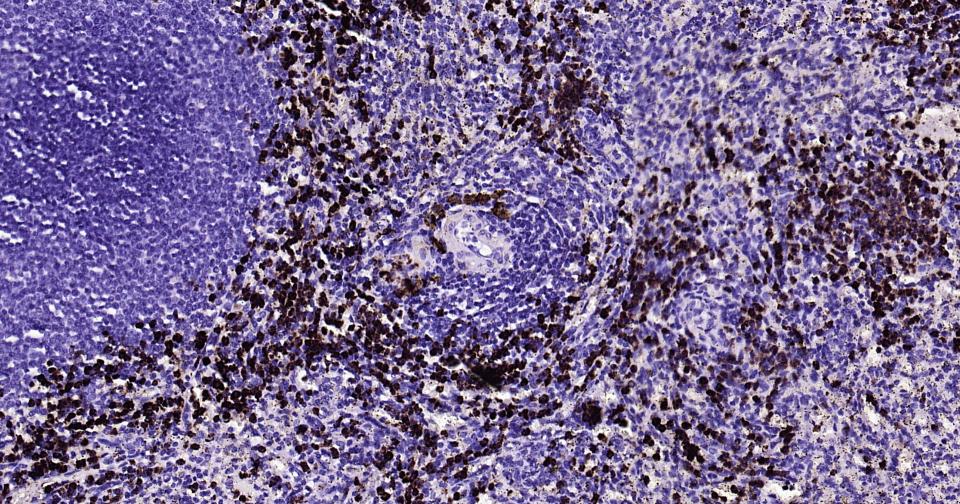

Cytolytic T lymphocytes (CTL) and natural killer (NK) cells share the remarkable ability to recognize, bind, and lyse specific target cells. They are thought to protect their host by lysing cells bearing on their surface 'nonself' antigens, usually peptides or proteins resulting from infection by intracellular pathogens. The protein encoded by this gene is crucial for the rapid induction of target cell apoptosis by CTL in cell-mediated immune response. [provided by RefSeq, Jul 2008]

| IHC-P | Human | 1:200-1000 | |